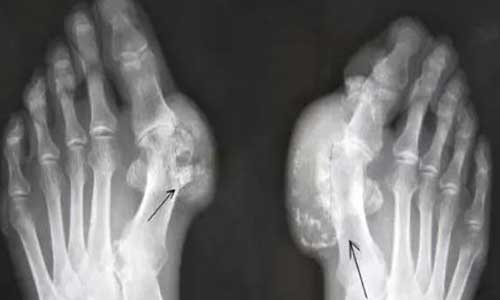

来自安阳市文峰区的孔先生来到我院(郑州痛风风湿病医院)后,自述痛风患病10年多,全身多处关节有大小不等痛风石,伴有患处关节活动功能受限,患病期间间断性服用药物治疗,治疗效果不佳,症状只是暂时性缓解...[详细]